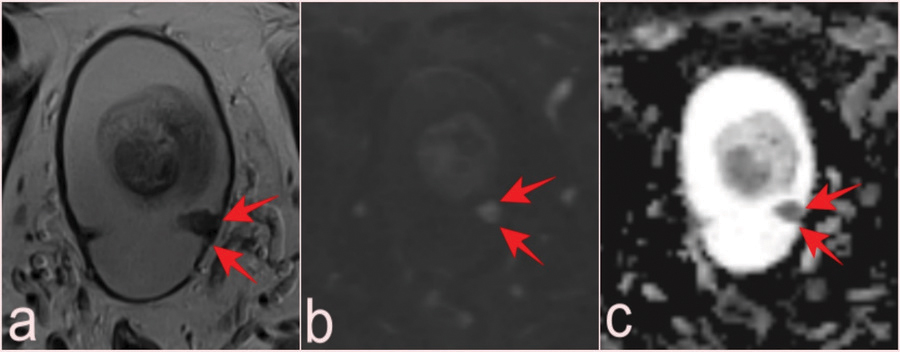

Figure 5

T2-WI (a), DWI (b), and ADC map (c) of a lesion with low-grade pTa tumor pathology reported as VI-RADS 1, which can be missed at the level of mucosal folds in a 69-year-old patient with prostate mpMRI after PSA elevation (arrows). ADC, apparent diffusion coefficient.